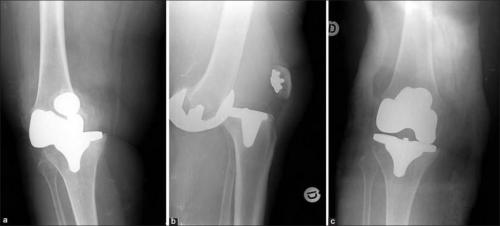

Эндопротезирование коленного сустава бывает тотальным, когда поврежденный хрящ заменяется протезом полностью, одномыщелковым меняется половина поврежденных структур и точечным- меняется непосредственно повреждённый участок хряща.

Реабилитация после эндопротезирования имеет первостепенное значение для обеспечения безболезненного функционирования сустава и улучшения качества жизни пациента. Операция попоказана для лечения болезненных и инвалидизирующих патологий, вызванных различными формами, тяжелыми травмами. Хирургом-ортопедом выполняется полная или частичная замена износившегося суставного соединения на его анатомически точную копию.

Большинство имплантов позволяют сгибаться коленному суставу, но не более чем на 110 градусов.